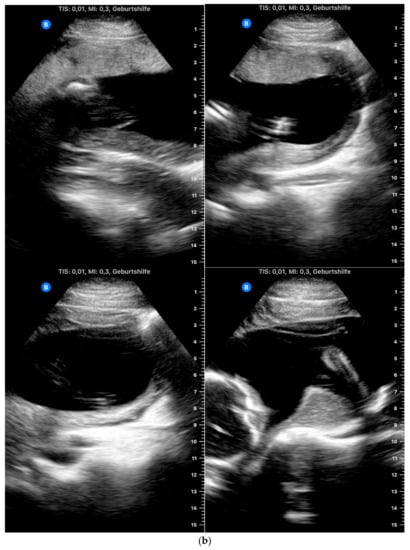

- If the participant was able to show the fetal heartbeat for at least one second during the video sequence lasting 30 s, it was marked as “target located.” For a satisfactory presentation of the fetal profile, the forehead, tip of the nose and chin had to be clearly visible (example in Figure 1). Images and videos taken by the participants in which the fetal profile was also not visible (n = 18) were excluded.

Figure 1. Requirements for satisfactory presentation of fetal profile: the forehead, tip of the nose and chin should be clearly visible. - For a satisfactory presentation of images and videos of the amniotic fluid, hypoechoic areas had to be clearly demarcated from parts of the fetus. The four images and four video sequences representing the amniotic fluid were evaluated separately. If the amniotic fluid was clearly displayed in one quadrant, the respective videos or image sequences were marked as “target located.” It was also examined whether the women were able to display the amniotic fluid in all four quadrants so that retrospective evaluation of a normal amount of amniotic fluid in a participant would be possible. Accordingly, the videos were marked as “4 out of 4 with sufficient quality” only if the amniotic fluid was visible in all four video sequences.